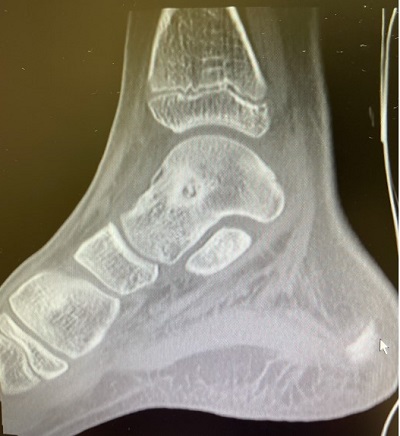

Durante 5 meses el paciente acude periódicamente a la consulta de pediatría de AP solicitando analgesia por dolor, destacando su facies triste y astenia. Ante esta evolución, desde AP se contacta con traumatología para realizar una resonancia magnética nuclear (RMN) de tobillo en la que se encuentran hallazgos sugestivos de osteoma osteoide subperióstico en cuello de astrágalo derecho, con nidus parcialmente mineralizado (Figuras 1 y 2). Se trata mediante ablación con radiofrecuencia, con adecuada respuesta y desaparición del dolor.

Figura 2. RM: tobillo con hallazgos sugestivos de osteoma osteoide subperióstien cuello de astrágalo derecho, con nidus parcialmente mineralizado